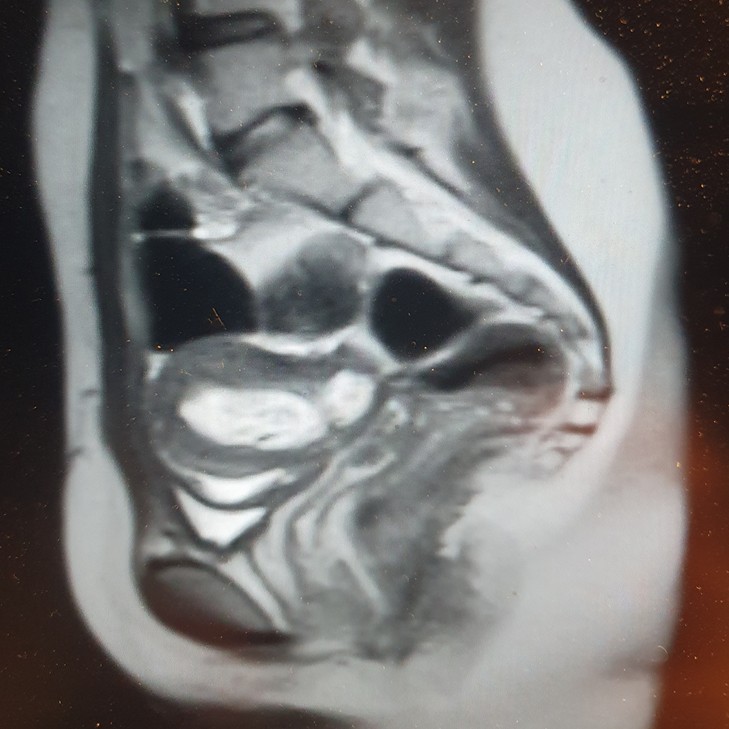

МРТ пациентки при поступлении в Центр Алмазова

Однако в течение последующего года наблюдения признаки нарушения оттока менструальной крови вновь стали появляться, а затем и прогрессировать. По данным МРТ была диагностирована нарастающая гематометра.